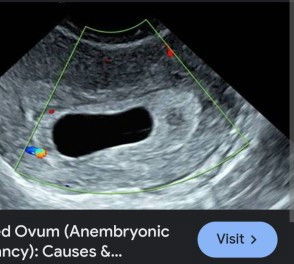

Blighted Ovum/ Bugok?

Mga mamsh hello po base sa lmp ko 8weeks & 3 days na ako nag pa trans v ako kahapon 6 weeks & 5 days lumabas pero bahay bata pa lang ang meron no baby no fetal pole bahay bata lang talaga sobrang clear na walang baby sabi ng ob ko balik daw ako after 1week dapat daw meron na pag balik ko normal po ba yun mga mii? yung asa picture po ganun lang po nakita sa akin clear na bahay bata lang wala kahit ano na nag pakita bahay bata lang talaga tapos sa mga pt ko 8 na pt positive naman po natatakot at kinakabahan na po kase ako di ako makatulog kakaisip na baka blighted ovum po ito hoping po na mag ka baby na βΉοΈβΉοΈ